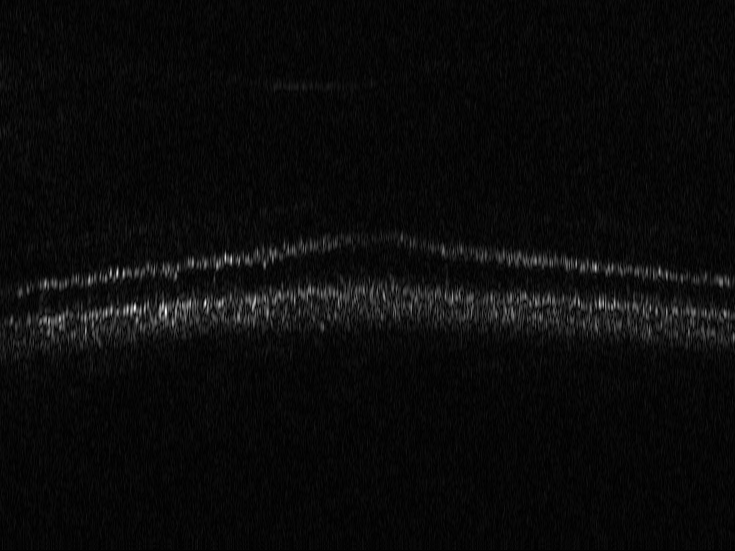

3.4 OCT

Optical coherence tomography (OCT) is a well established imaging technique based on low-coherence interferometry that enables volumetric imaging of biological tissue at high resolution (citep \@BBN(Pircher, 2018)). Light is split into a reference and a sample arm, recombined after being backreflected by a mirror and backscattered at different depths of the sample, in the respective paths. Using Fourier domain OCT (citep \@BBN(Fercher et al., 1995)), a tomographic image of the sample is reconstructed by spectral analysis of the resulting interference patterns. In order to achieve optimal axial resolution (i.e. resolution in depth), it is essential to match dispersion between the two arms of the interferometer (citep \@BBN(Drexler et al., 2008)). This can be achieved on the one hand by carefully matching the length of the arms and the corresponding dispersive materials and on the other hand by numerical methods in the reconstruction process (citep \@BBN(Wojtkowski et al., 2004)). OCT was originally developed for imaging of the retina and, while there are many other applications of OCT available, its highest impact is to this day in ophthalmology, where this technology plays a critical role in correct diagnosis (citep \@BBN(Pircher, 2018)).

3.4.1 Reconstruction problem

Most commonly, OCT processing algorithms compute intensity images from the recorded spectral data. Standard algorithms include a step that performs numerical dispersion compensation. Methods are available which automatically determine the correct dispersion compensation parameter (citep \@BBN(Wojtkowski et al., 2004)), but the stability of automatic numerical dispersion compensation methods under varying imaging conditions is not fully understood. Besides the dispersion parameter, there exist also algorithms that provide geometrical corrections within the reconstruction process, see e.g. (citep \@BBN(Shirazi et al., 2020)), namely the correction of rotation introduced by eye motion and correction of the curvature of the retina. Automatic parameter selection for the geometric corrections is a challenging task which has so far not been addressed and therefore these parameters are usually set manually, which is very time-consuming especially in the case of clinical studies where often a large number of patients and imaging locations is included.

It is important to note that errors in the considered corrections have varying impact on the usability of the resulting intensity data. Errors in the geometrical corrections can be fixed in an additional post-processing step after the reconstruction. An incorrect choice of the dispersion compensation parameter however results in deteriorated axial resolution which cannot be corrected in post-processing. The OCT processing of the spectral data would have to be repeated. Therefore, OCT image data with faulty dispersion compensation should be evaluated as having worse image quality than image data with faulty rotation and curvature compensation. A metric that is able to distinguish between the image quality criteria at hand would be helpful to automatically find the correct parameters of the algorithm in a robust manner.

3.4.2 Data

We use here representative image data obtained using an adaptive optics (AO) supported spectral domain OCT system (citep \@BBN(Brunner et al., 2021)). Cross-sectional images (B-scans) were retrieved from two AO-OCT volumes recorded in a young healthy volunteer (27 years, female, right eye) with a field of view of approximately 4×4superscript4superscript44^{\circ}\times 4^{\circ} (corresponding to  1.4×1.4mm1.41.4𝑚𝑚1.4\times 1.4mm on the retina). Different imaging locations and focus settings were considered. One data set was recorded in the fovea with the focus of the imaging beam set to the posterior retina and one data set close to the optic disc with the focus shifted to the anterior retina. An algorithm including dispersion compensation and geometrical corrections was employed (citep \@BBN(Shirazi et al., 2020)) for the reconstruction. The images are shown on a linear intensity grey scale. The reference images, (a) in Figure 9 and 10, were obtained by manually optimizing over the parameters that define the compensation of dispersion, rotation and curvature, respectively. The examples in Figure 9 and 10 compare the chosen reference to three sub-optimal reconstructions, where (b) had a bad choice for the rotation correction parameter, (c) for the curvature correction parameter and (d) for the dispersion compensation parameter.

Refer to caption

(a) Reference

(b) (26.88, 0.71, 0.05)

(c) (26.84, 0.72, 0.04)

(d) (29.94, 0.77, 0.06)

Figure 9: OCT reference reconstruction (a) and reconstructions with sub-optimal parameters (b)-(d) leading to geometric deviations (b)-(c) and low resolution (d). Here, (d) is wrongly judged as best reconstruction by SSIM and PSNR, LPIPS is able to ignore the small spatial deviations.

(b) (25.20, 0.55, 0.04)

(c) (26.49, 0.66, 0.03)

(d) (27.78, 0.70, 0.06)

Figure 10: OCT reference reconstruction (a) and reconstructions with sub-optimal parameters (b)-(d) leading to geometric deviations (b)-(c) and low resolution (d). Here, (d) is wrongly judged as best reconstruction by PSNR and SSIM, LPIPS is able to ignore the small spatial deviations.

FR-IQA mismatches

Good dispersion compensation should provide images with a depth resolution that is optimized for the system at hand. In the ophthalmic application of AO-OCT, this high axial resolution allows for the visualization and identification of the different retinal layers (citep \@BBN(Shirazi et al., 2020; Brunner et al., 2021; Wojtkowski et al., 2004)), different retinal layers and structures, such as blood vessels. In the first example Figure 9 the clear separation of the different layers in the posterior retina, such as the photoreceptor bands and the retinal pigment epithelium, is crucial for clinicians/researchers who investigate the structure and function of the healthy and the diseased human retina (citep \@BBN(Jonnal et al., 2014)). Therefore, in this example, the reconstruction shown in Figure 2 (d) should have clearly been rated the lowest as the axial resolution is the lowest because of faulty dispersion compensation, which cannot be fixed by further post-processing. In the second example Figure 10, a cross-sectional view of three retinal vessels which are embedded in the nerve fibre layer is given. Changes in the thickness of vessel walls are an important early biomarker for retinal diseases such as diabetic retinopathy, cf. (citep \@BBN(Bakker et al., 2022)). Again, the reconstruction with faulty dispersion compensation shown in Figure 10(d) should have been rated the lowest. The loss in axial resolution worsens the visualisation of the vessel walls and would lead to inaccurate measurements of the vessel wall thickness. In the current version of the algorithm the parameters which determine the amount of dispersion, rotation and curvature compensation applied by the reconstruction algorithm have to be set manually. Therefore, automated evaluation would be very helpful to fasten the process. The standard metrics are not suitable here, as PSNR and SSIM wrongly assess that reconstruction as the best, and, as expected, penalize harder the geometric deviations in (b) and (c). The geometric deviations are not beneficial, but could be fixed by post-processing unlike image (d).